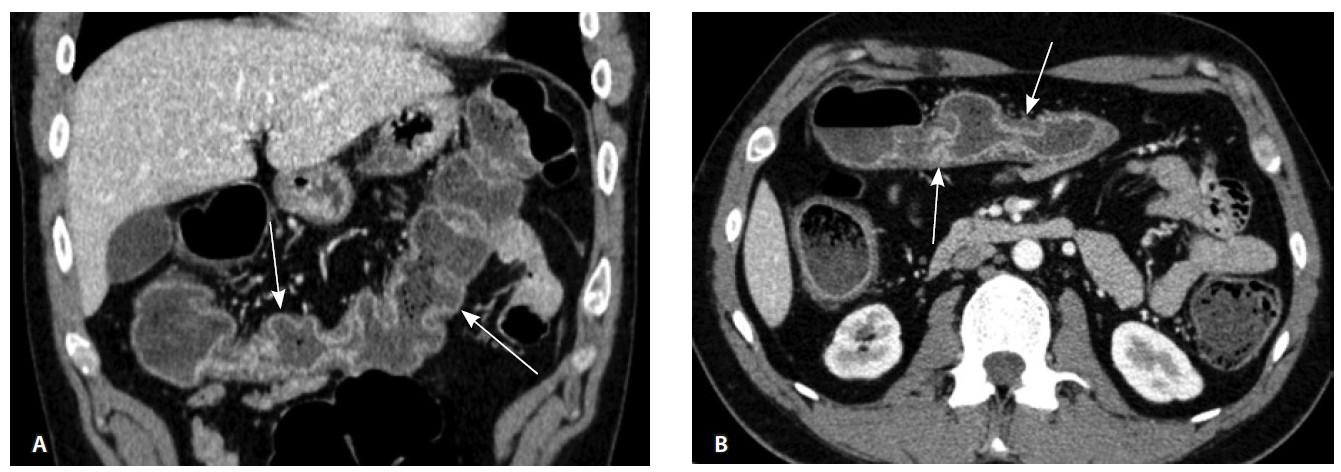

Назначена ГИБТ адалимумабом (препарат Хумира) по стандартной схеме 160 мг п/к (неделя 0), 80 мг п/к (неделя 2) с последующим плановым поддерживающим режимом 40 мг п/к каждые 2 недели. Через 9 месяцев установлена эндоскопическая ремиссия, однако сохранялась концентрация фекального кальпротектина более 2000 мкг/г. Через год жалобы возобновились, тогда же впервые была выявлена задняя анальная трещина. Выполнена магнитно-резонансная энтерография, обнаружены воспалительные изменения, характерные для БК (рис. 2 и 3).

Рис. 2. Магнитно-резонансная энтерография, Т2-взвешенное изображение: А, В – фронтальная проекция; Б – аксиальная проекция. Наблюдается отсутствие гаустрации в восходящем отделе ободочной кишки, утолщение ее стенки до 5 мм (стрелка), снижение магнитно-резонансного сигнала от прилежащих отделов клетчатки, ее неоднородность (пунктирная стрелка), увеличение лимфатических узлов до 6 см в диаметре по ходу сигмовидной кишки (стрелки)